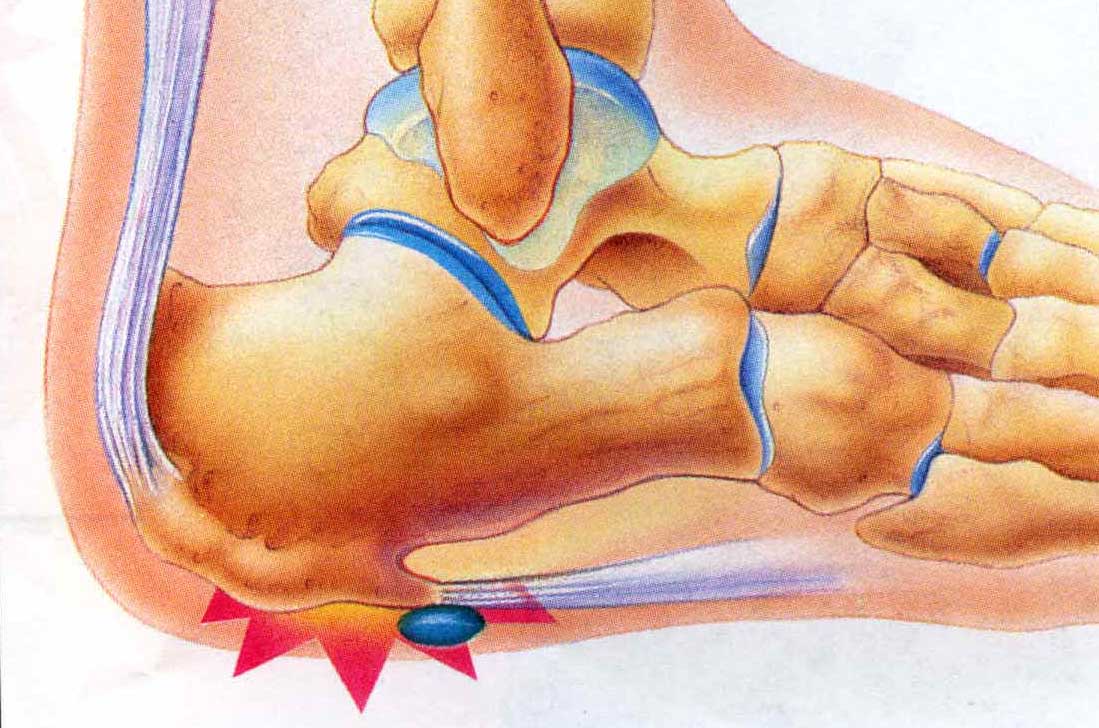

Heel Pain

Heel pain is a very common foot complaint and may involve injury to the bone, fat pad, ligaments, tendons or muscles.